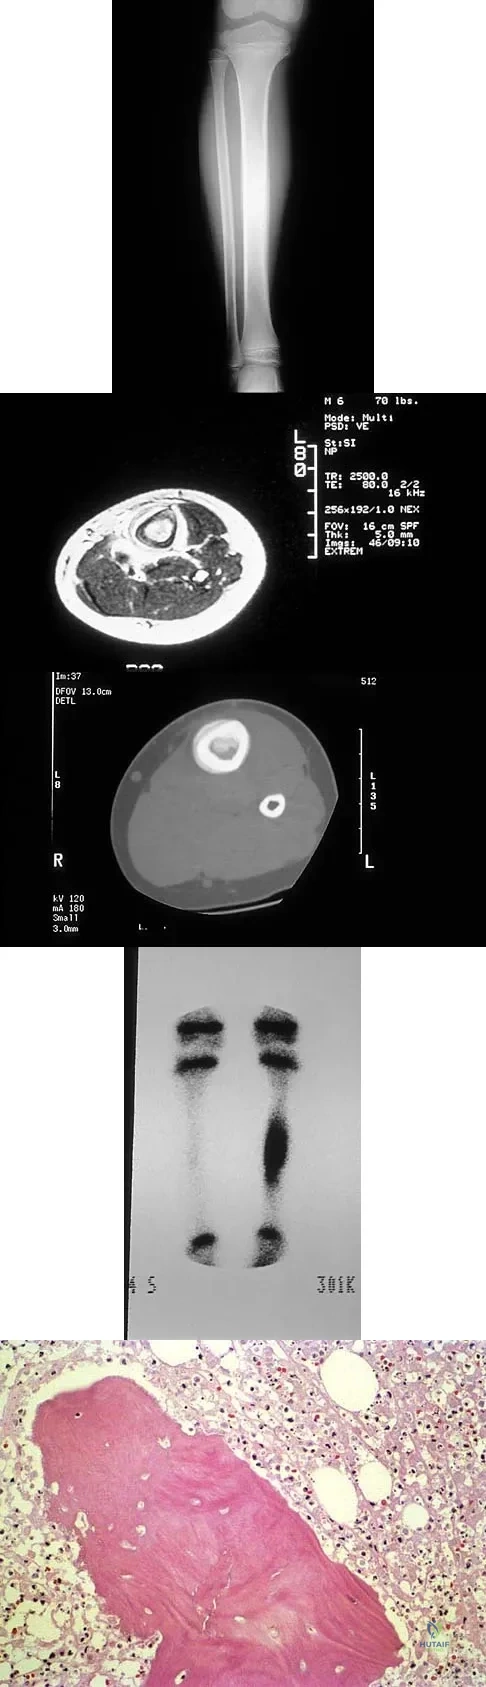

A 6-year-old boy has leg pain. A radiograph, MRI, CT, and bone scans, and a biopsy specimen are shown in Figures 14a through 14e. What is the most likely diagnosis?

Explanation